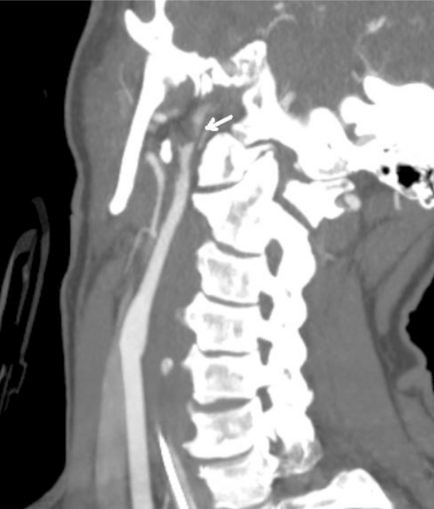

简介:当采用适当的筛查标准时,钝性脑血管损伤(BCVI)在所有钝性创伤中占1-2.7%。相当数量的BCVI患者有潜伏期或无症状期,在此期间,基于适当使用血管造影的治疗干预可能会降低缺血性卒中的风险。方法:病例报告和文献复习。结果:一名42岁的女性从摩托车上摔下来,在急诊室神经系统完好。在非对比计算机断层扫描(CT)上发现累及颈椎横孔的骨折,但未进行BCVI血管造影筛查。随后,她患上了缺血性中风,导致严重残疾。本文回顾了针对BCVI筛查标准的使用及后续治疗的已发表研究。结论:BCVI可导致缺血性脑卒中显著的发病率和死亡率。BCVI与缺血性脑卒中的发生之间往往有一段潜伏期。特定的危险因素可用于确定需要导管或CT血管造影筛查的患者。抗血栓药物治疗是BCVI的主要治疗方法,可以降低缺血性卒中的发生率。钝性创伤患者无症状BCVI的识别和治疗可以预防缺血性脑卒中的主要是年轻人群。

Introduction: Blunt cerebrovascular injury (BCVI) is found in 1-2.7% of all blunt trauma when appropriate screening criteria are employed. A significant number of patients with BCVI have a latent, or asymptomatic period, in which therapeutic intervention based on the appropriate use of angiographic imaging may decrease the risk of an ischemic stroke. Methods: Case report and review of literature. Results: A 42 year old woman suffered a fall off a motorcycle and was neurologically intact in the emergency room. Fractures involving the transverse foramen of cervical vertebrae were found on non-contrast Computed Tomography (CT) but screening for BCVI with angiographic imaging not performed. She subsequently suffered an ischemic stroke resulting in significant disability. Published studies that address the use of screening criteria for BCVI and subsequent management are reviewed. Conclusion: BCVI results in significant morbidity and mortality attributable to ischemic stroke. There is often a latent period between BCVI and occurrence of ischemic stroke. Specific risk factors can be used to identify patients requiring screening with catheter or CT angiography. Treatment with antithrombotic agents is the mainstay of treatment of BCVI and may reduce the rate of ischemic stroke. Identification and treatment of asymptomatic BCVI in blunt trauma patients may prevent ischemic stroke in a predominantly young population.